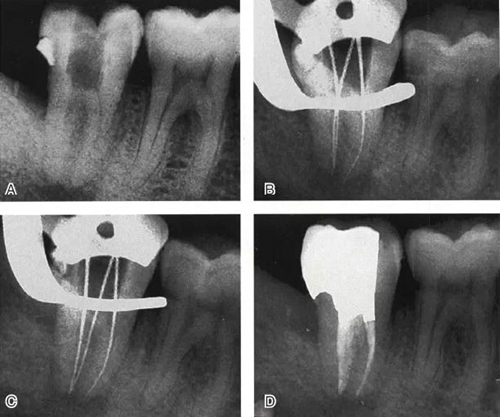

根管充填是C形根管治療成功與否的最重要因素。充填C形根管系統(tǒng)時(shí),近舌及遠(yuǎn)中根管可以進(jìn)行常規(guī)充填。關(guān)于狹區(qū)的充填,更適合以熱牙膠垂直加壓充填,這種方法可使牙膠到達(dá)根管系統(tǒng)的每一死角(圖4~7)。

圖6 Ⅱ型C形根管治療典型病例,A:初尖銼片,B:主尖銼片,C:根充片,D:術(shù)后片